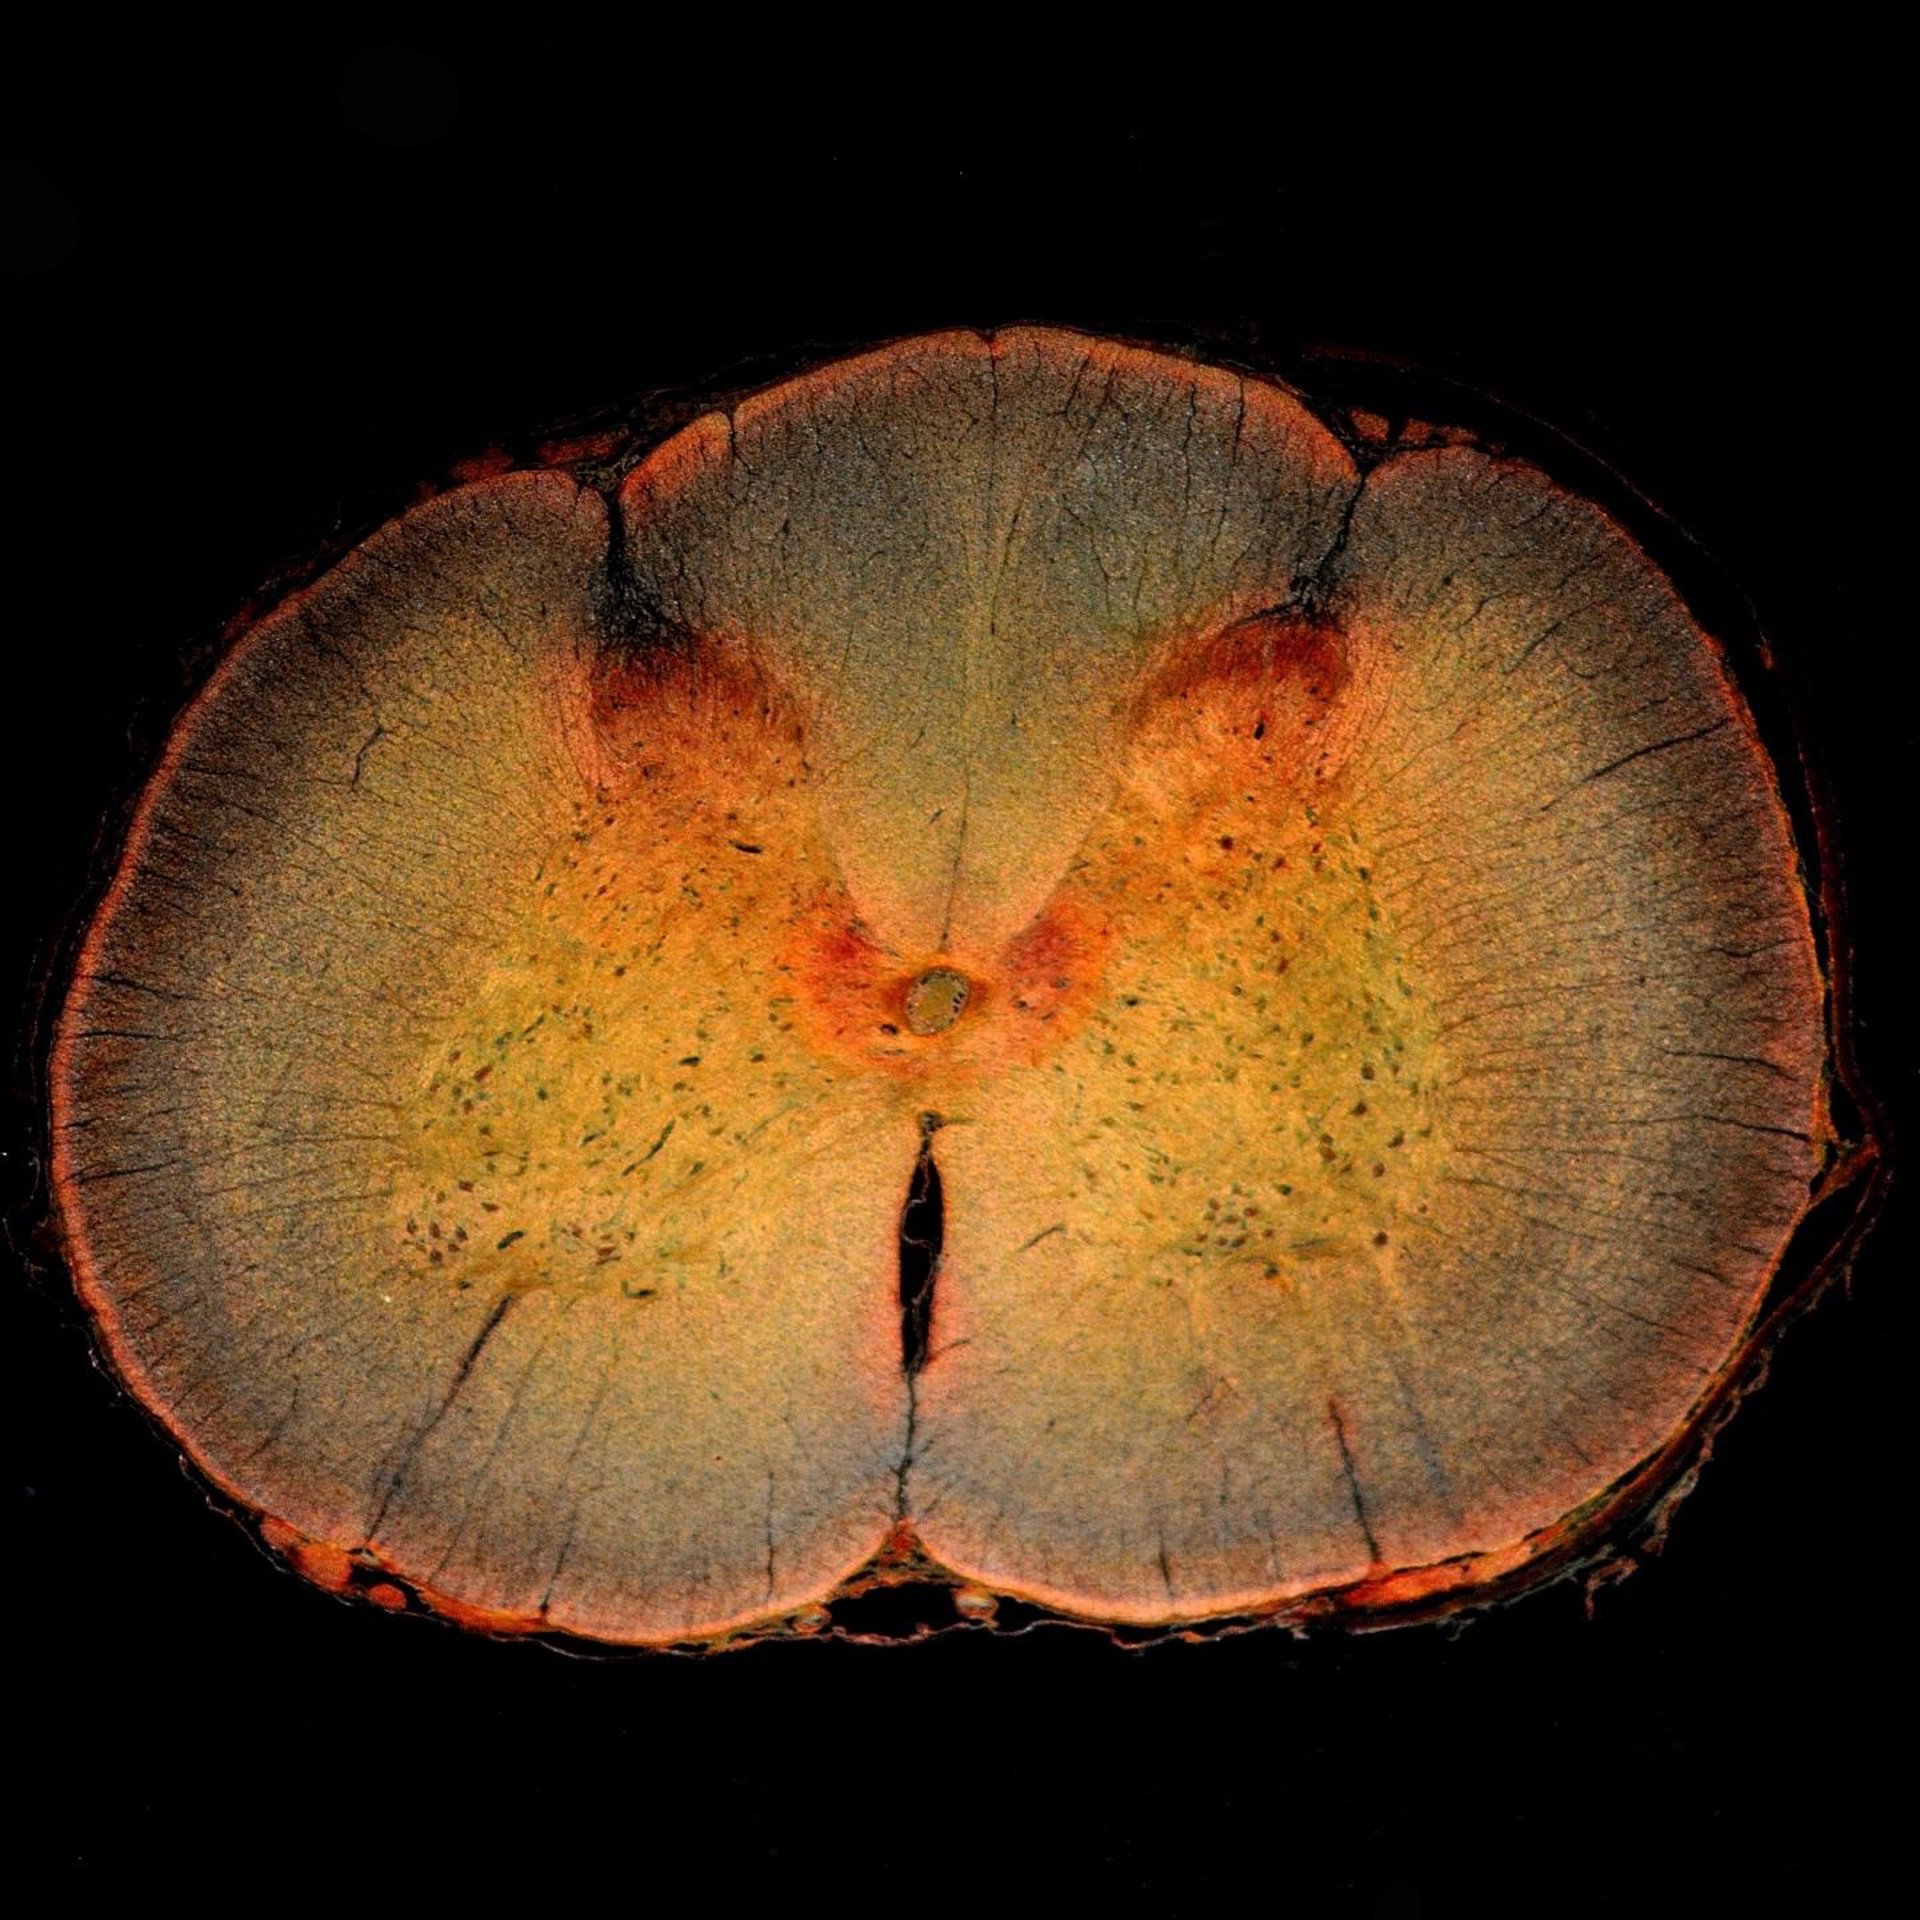

Las células gliales llevan a cabo una serie de funciones de apoyo y mantenimiento, y un tipo en particular, la célula glial astrocítica, tiene la capacidad única de formar tejido cicatricial alrededor de las neuronas dañadas. La presencia de tejido cicatricial se asocia con efectos inhibidores sobre el recrecimiento de neuronas maduras dañadas por una lesión de la médula espinal.

Sin embargo, la evidencia reciente sugiere que estos efectos inhibidores son reversibles, y en un nuevo trabajo, científicos de la Facultad de Medicina Lewis Katz de la Universidad de Temple (LKSOM) y la Universidad de Pensilvania muestran que las células gliales astrocíticas pueden de hecho desempeñar un papel importante en facilitando la reparación de neuronas.

En experimentos iniciales, confirmaron lo que habían indicado estudios anteriores, que los efectos negativos de la actividad de las células gliales sobre la regeneración de axones son de hecho reversibles. Pero los investigadores también encontraron que el cambio entre efectos positivos y negativos sobre el recrecimiento de axones está directamente relacionado con el estado metabólico de las células gliales.